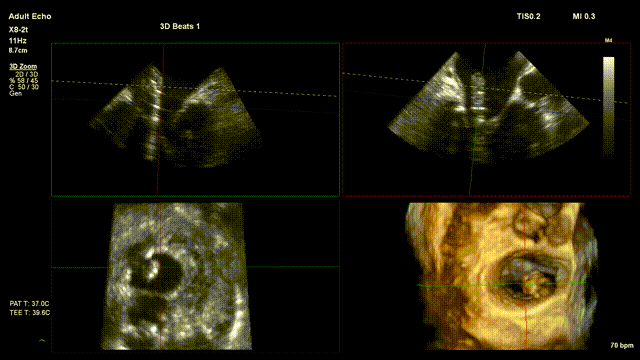

本网讯(通讯员 李薇)提到心脏检查,很多人会想到超声。但你知道吗?您是否听说过心脏超声检查?传统心脏超声如同给心脏拍 “平面照片”,而三维经食道超声心动图(简称 “三维食道超声”),能为心脏打造 “3D 电影” 般的立体影像,让心脏细节清晰呈现,助力医生精准排查问题,为心脏健康保驾护航。

普通超声是平面图像,医生需要“脑补”心脏的立体结构;而三维食道超声能生成360°旋转的心脏模型,就像用3D打印机还原了一颗跳动的心脏,能够清晰得显示心脏的四个腔室、瓣膜(如二尖瓣、主动脉瓣)的形态,连毫米级的缺损或脱垂都能发现。三维食道超声还能动态观察心脏收缩、舒张时的运动状态,计算心功能指标,判断心脏泵血是否正常。通过彩色多普勒技术,直观显示血液在心脏内的流动方向和速度,快速发现反流、狭窄等问题。